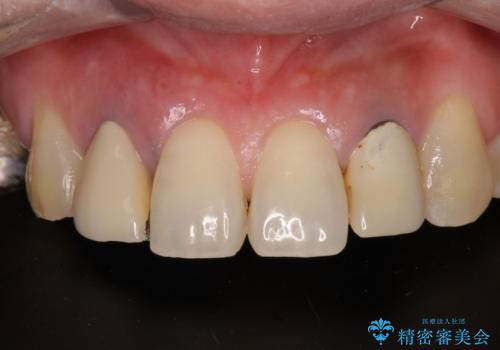

放置した破折歯 即時・早期のインプラント埋入による補綴治療

セオリーとしては、インプラント補綴治療により奥歯の咬み合わせを確立してから、前歯部の処置を行うことになりますが、初めてのインプラント治療であることや、前歯部の見た目が気になっていることから、前歯の抜歯即時埋入インプラントによる補綴治療を先行して行い、並行して奥歯のインプラント治療を進めて行くこととしました。

抜歯即時埋入インプラントによる補綴治療の特徴は、短期間であることや処置数が少ないことが挙げられます。また、表側の歯肉の陥凹を避けることができるというメリットがあります。しかしながら、今回は歯根破折の程度が酷く、やや膨らみを失うこととなりましたが、スムーズに治療を終えることができました。